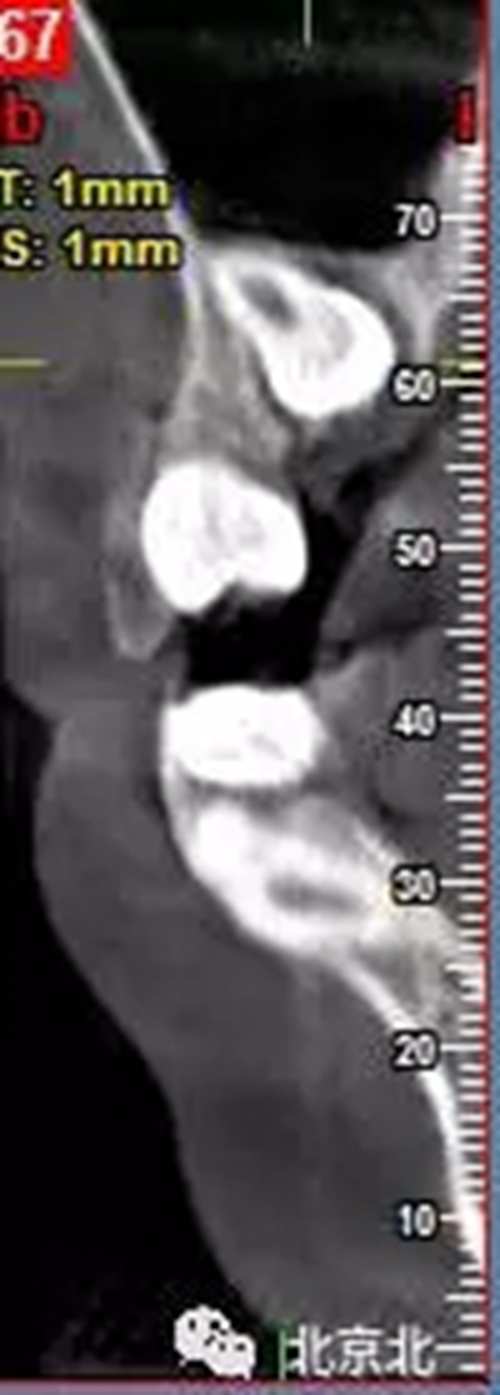

圖一:拔牙前影像片(CBCT)

總結(jié):埋伏牙如果直接硬撬可能會(huì)導(dǎo)致牙槽骨骨折。需要采用微動(dòng)力系統(tǒng)將牙齒有絲分裂后拔除。